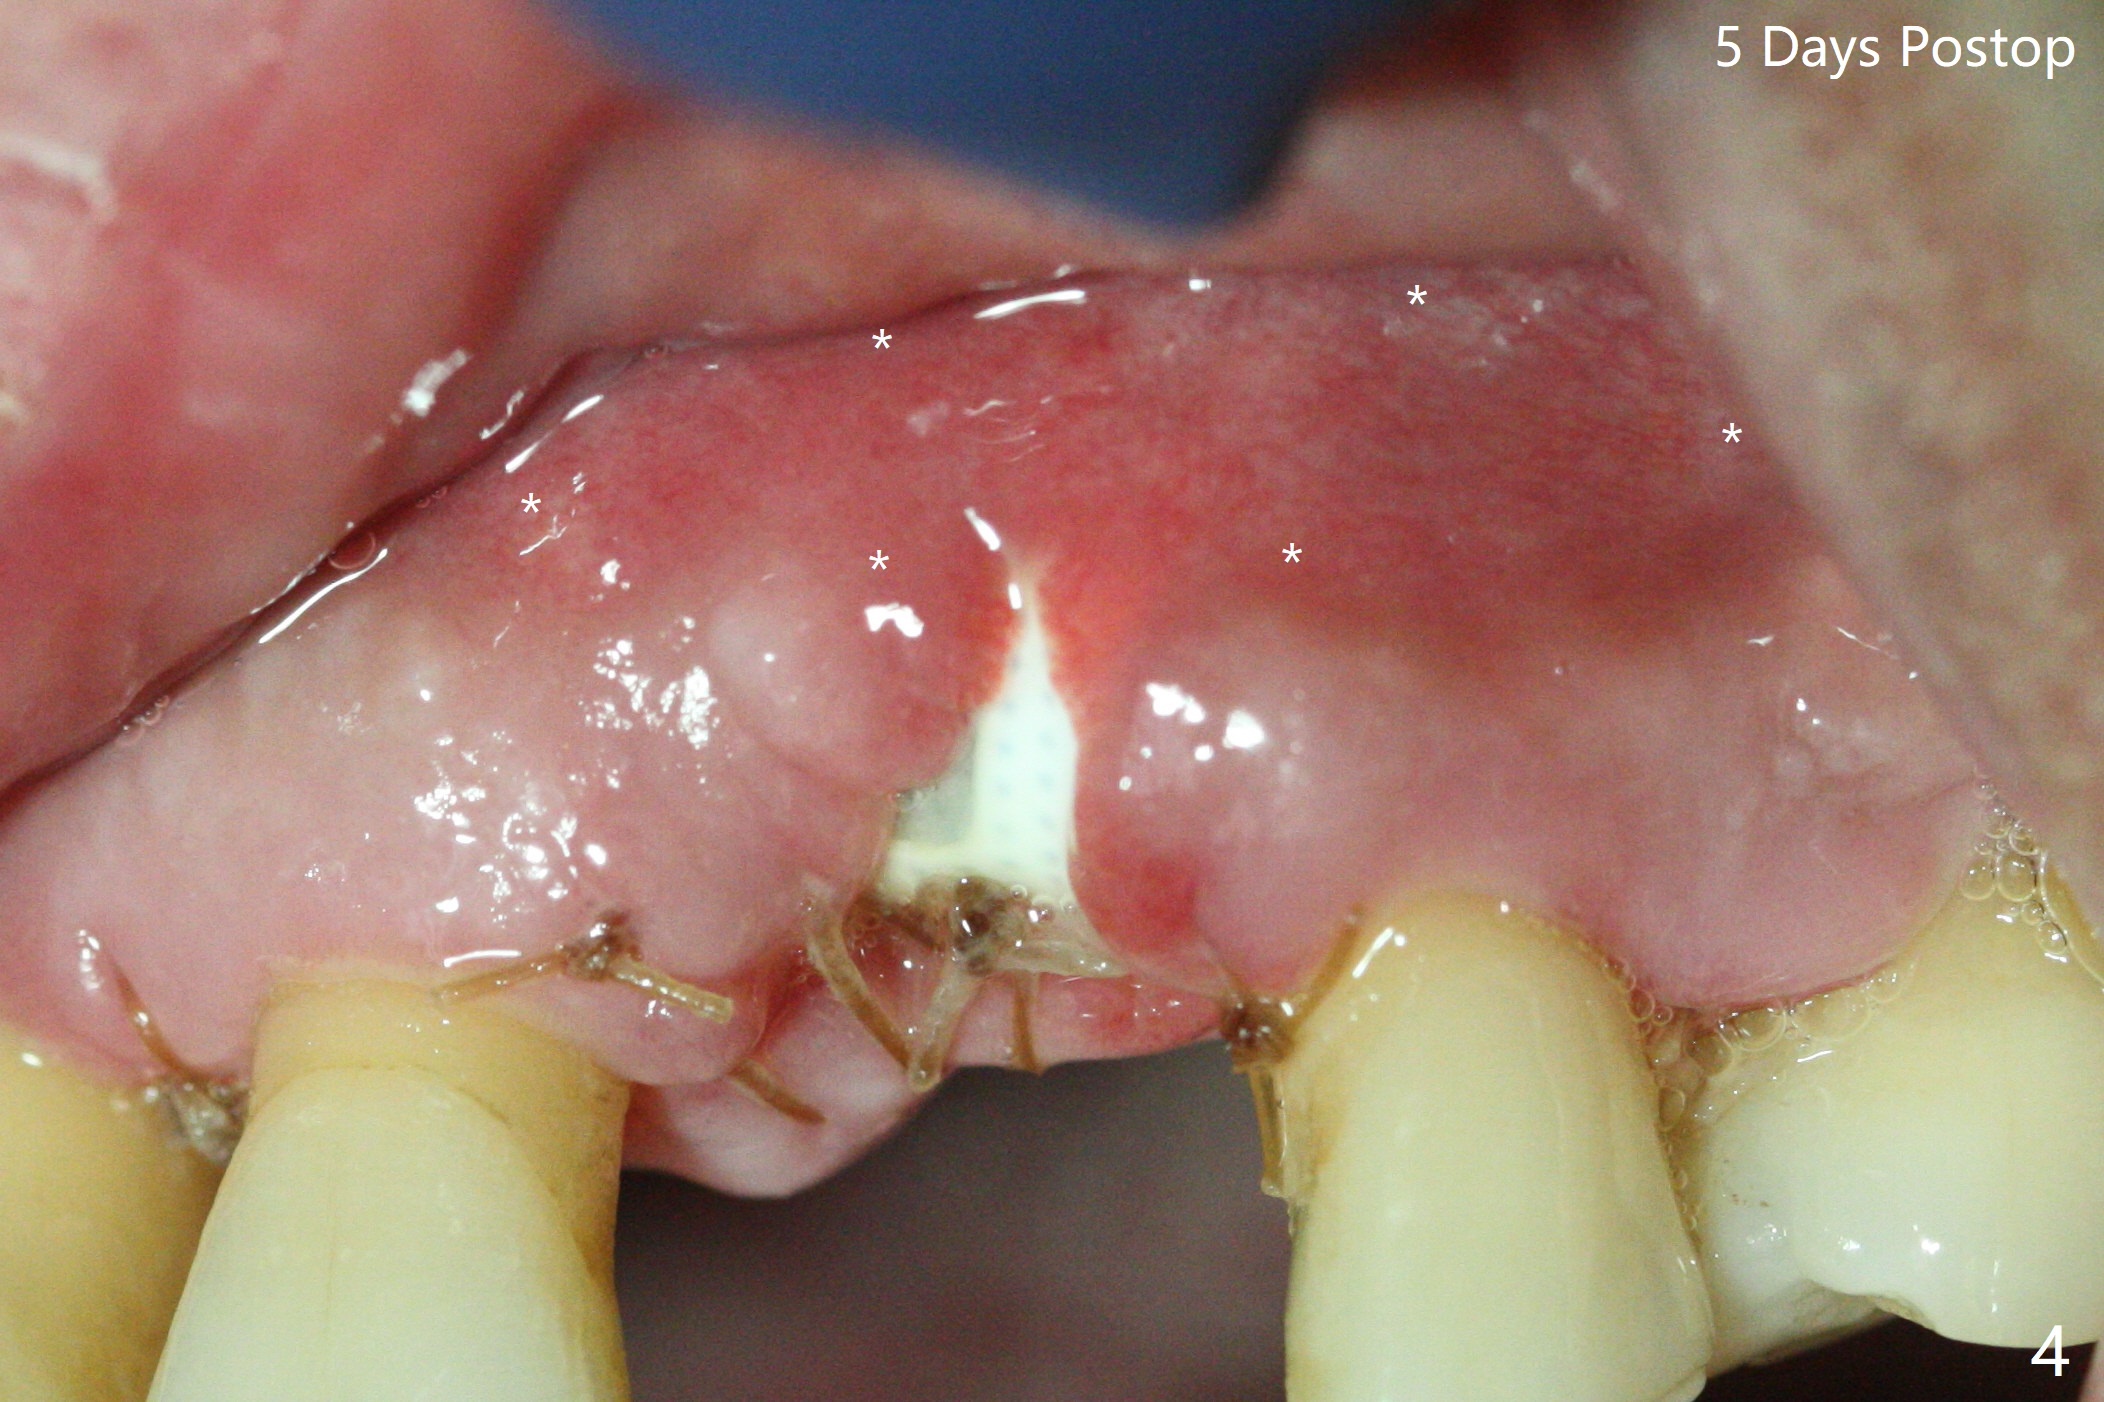

A 67-year-old man requests extraction of the loose tooth #9 (Fig.1). After extraction, the labial plate is found to be missing. With incision, allograft is kept in place with a 12x24 mm anterior narrow Cytoplast and 4-0 Chromic gut suture (Fig.2). Periodontal dressing dislodges in 2 days. The wound dehisces transversely 5 days postop (Fig.3 arrows), whereas the wound was open buccopalatal when the sutures were placed. Probably due to extensive dissection, the erythematous mucosa is large (Fig.4), although asymptomatic. When X-ray shows V-shaped bony defect (Fig.1 (PA), 5 (Pan), 6 (CT)), do not dissect the overlying thin buccal gingiva, which is most likely to dehisce. In fact immediate implant with guide appears to be more conservative, since there is no pressure against the buccal gingiva (Fig.7,8). To be more ideally, the implant could be placed more coronally, longer (13 mm instead of 11.5, Fig.9,10) and narrower (3.5 mm instead of 4.0 mm, Fig.11 (red circles: bone graft)).